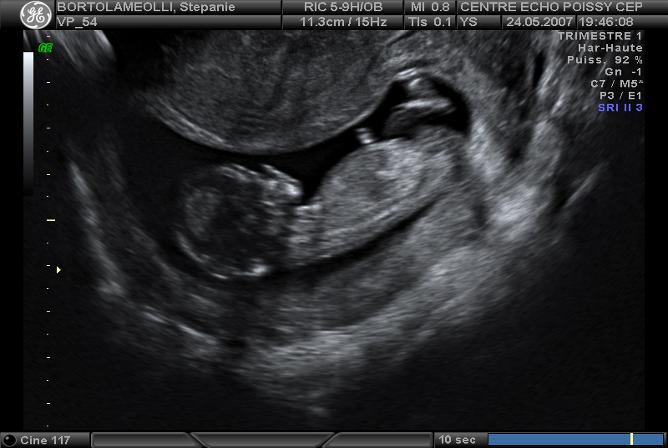

Echographies